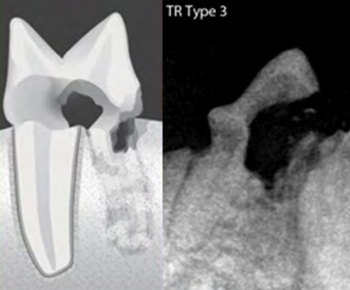

치아흡수병변 TYPE 및 예시

TYPE 3

치아흡수병변의 모습과 치아엑스레이 영상(Type3)